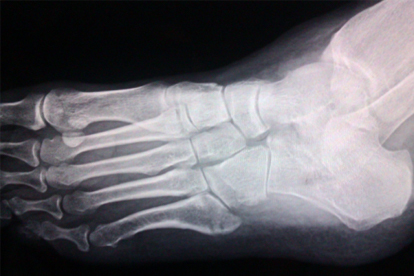

脚骨折后的恢复时间差异较大,轻微骨裂可能6-8周即可尝试部分负重,而粉碎性骨折或关节内骨折需12周以上。骨折初期1-2周需严格制动,通过石膏或支具固定防止移位。2-4周后经影像学检查确认骨痂形成,可在医生指导下开始踝关节被动活动。4-6周后逐步进行无负重肌肉训练,如足趾屈伸运动。6周后根据愈合情况使用拐杖辅助部分负重,8-12周过渡到完全负重行走。康复期间需避免过早承重导致二次损伤,定期复查X线片观察愈合进度。

固定制动需保持石膏干燥清洁,观察肢体末端血运和感觉。冰敷每日3-4次,每次15分钟减轻肿胀疼痛。抬高患肢需高于心脏水平,促进静脉回流。饮食应增加钙质、维生素D和优质蛋白摄入,如牛奶、鱼类、豆制品。功能锻炼从非负重活动开始,逐步增加踝泵运动、抗阻训练。定期复查可及时调整康复方案,发现延迟愈合或畸形愈合需干预处理。